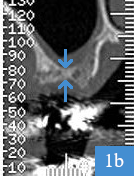

4 mois après la greffe osseuse, largeur de 9,5 mm

Dentascanner 4 mois après la greffe

5 : largeur de la crête osseuse mesurée à 9,5 mm ; pose d'un implant possible